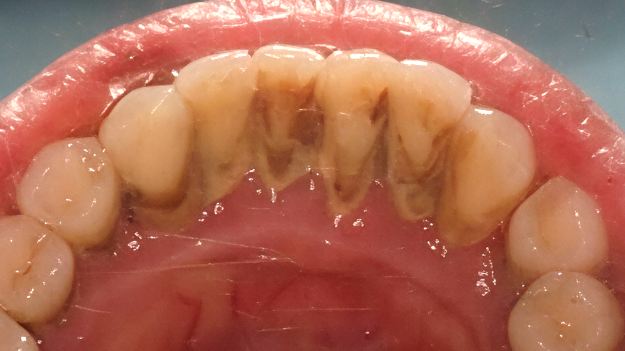

洗牙前VS洗牙后

(徐静医生病例)

洗牙,是口腔护理的基础!许多人不知道,洗牙洗的不仅是“脏东西”,更是牙结石、软垢、菌斑这些导致牙齿发黄、牙龈发炎的“元凶”!通过专业洗牙(龈上洁治),确实能有效去除大部分外源性着色和致病因素,恢复“红(牙龈)白(牙齿)美学”,让口腔呈现自己真实的美貌和健康。